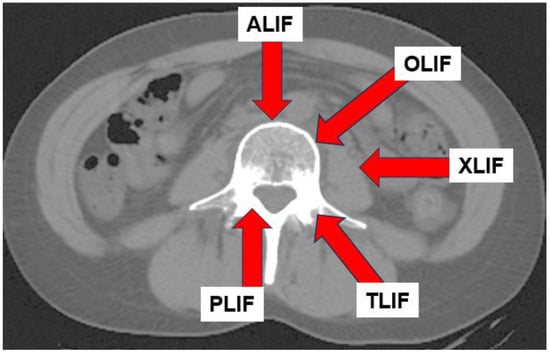

In recent years, lateral lumbar interbody fusion (LLIF) has become more popular, with extreme lateral interbody fusion (XLIF) and oblique lumbar interbody fusion (OLIF) being the most common LLIF techniques. These techniques are less invasive than conventional posterior lumbar interbody fusion (PLIF) [] and transforaminal lumber interbody fusion (TLIF) [] and allows for the insertion of a larger cage, which allows for a greater restoration of lumbar lordosis [,].

In physical therapy, it is necessary to identify the path of entry for spinal fusion and to understand the muscles involved [] (Figure 9). Muscle atrophy results from denervation due to surgical invasion of the multifidus and erector spinae muscles for posterior approach (PLIF and TLIF) [,]. LLIF incises the external oblique, internal oblique, and transversus abdominis muscles, resulting in post-operative muscle weakness (Figure 10). Hence, rehabilitation should be focused according to the procedure performed, as trunk extension and trunk flexion strength strongly correlate with ODI [].

Figure 9.

The path of entry for different spinal fusion techniques.